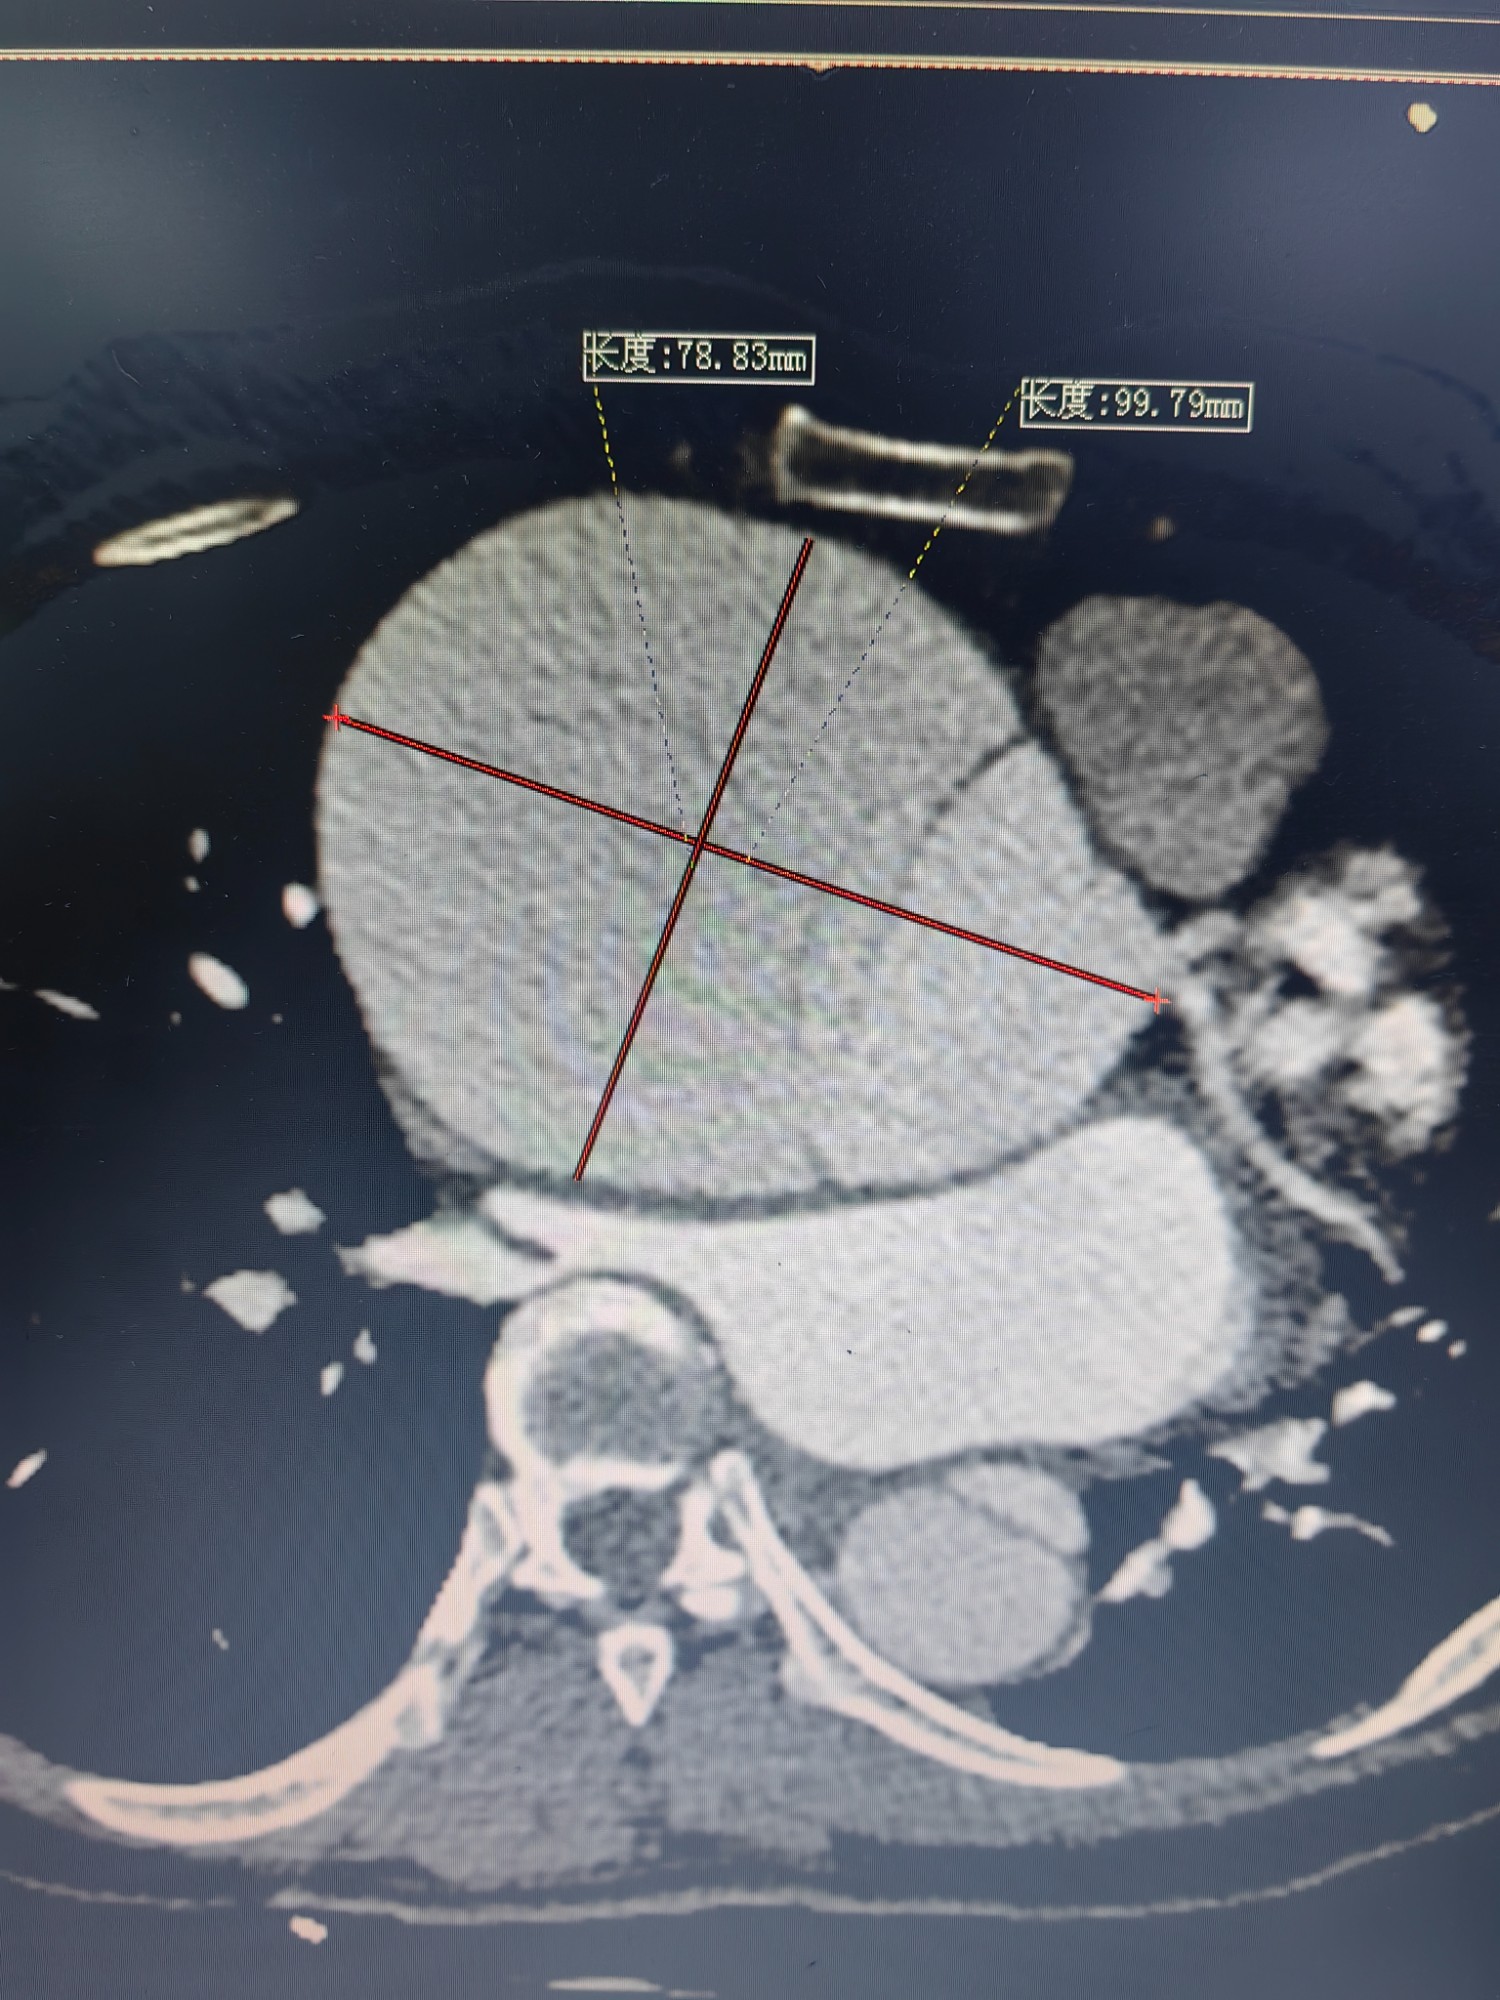

俗语说:“麻绳专挑细处断,噩运只找苦命人”。2023年4月底,李女士开始出现活动后气促、心悸症状,夜间阵发性呼吸困难,只能端坐呼吸,不能平卧睡眠。她自行口服感冒药后症状也迟迟没得到缓解,于是到广西壮族自治区南溪山医院心血管内科住院治疗,却不幸被确诊为A型主动脉夹层及马凡综合征,被紧急转到心脏大血管外科。CT血管造影(CTA)检查提示李女士为A型主动脉夹层(慢性),升主动脉增粗接近10cm,而健康人群的主动脉只有3cm左右;左冠状动脉上方有3cm的巨大主动脉破口,右冠状动脉则是直接内外膜离断,主动脉远端真腔受压极小。

2、手脚细长、血压脉压差很大、术前CTA三维、根部严重扩张。(1)

3、手脚细长、血压脉压差很大、术前CTA三维、根部严重扩张。 (2)

4、手脚细长、血压脉压差很大、术前CTA三维、根部严重扩张。 (3)

5、手脚细长、血压脉压差很大、术前CTA三维、根部严重扩张。(4)